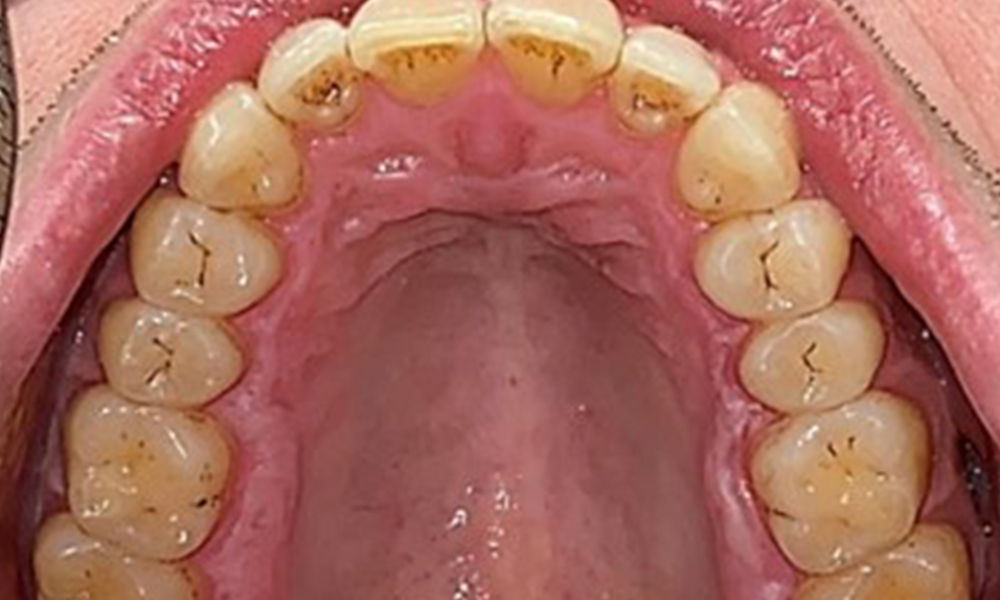

Okklusalansicht Oberkiefer

Abb. 3: Okklusalansicht Oberkiefer, © Dr. R. Krapf

Dental zeigt sich ein vollbezahntes Gebiss mit 28 Zähnen. Auffällig sind Erosionen und Attritionen

(Abb. 4, Abb. 5). Der Patient trägt seit vielen Jahren nachts eine Schiene mit adjustiertem Aufbiss aufgrund Bruxismus. Die Erosionen sind auf den langjährigen Konsum isotonischer Getränke zurückzuführen. Parodontaler Knochenverlust und aktive kariöse Läsionen sind nicht vorhanden.